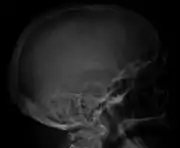

Skull X-ray showing multiple lucencies due to multiple myeloma

Bone pain

Bone pain affects almost 70% of people with multiple myeloma and is one of the most common symptoms.[2]: 653 [22] Myeloma bone pain usually involves the spine and ribs, and worsens with activity. Persistent, localized pain may indicate a pathological bone fracture. Involvement of the vertebrae may lead to spinal cord compression or kyphosis. Myeloma bone disease is due to the overexpression of receptor activator for nuclear factor κ B ligand (RANKL) by bone marrow stroma. RANKL activates osteoclasts, which resorb bone. The resultant bone lesions are lytic (cause breakdown) in nature, and are best seen in plain radiographs, which may show "punched-out" resorptive lesions (including the "raindrop" appearance of the skull on radiography). The breakdown of bone also leads to the release of calcium ions into the blood, leading to hypercalcemia and its associated symptoms.[23]